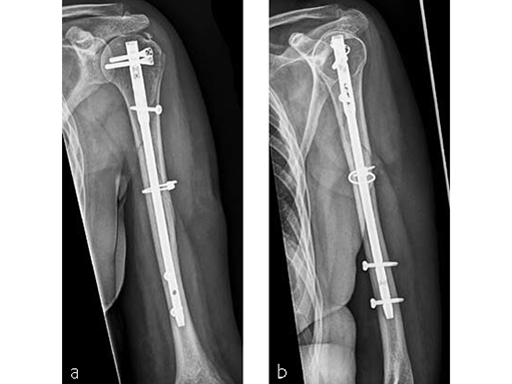

Case 4: AO 12C1 fracture following fall

A 54-year-old woman, and otherwise healthy patient, fell during her holidays and sustained an AO 12C1 fracture. There was no major soft tissue trauma. Other lesions: avulsion at the 5th metatarsal base, and concussion. Surgery took place on day 9 after the accident. The patient left the hospital the day after surgery.

Case provided by Markus Wambacher, Innsbruck, Austria